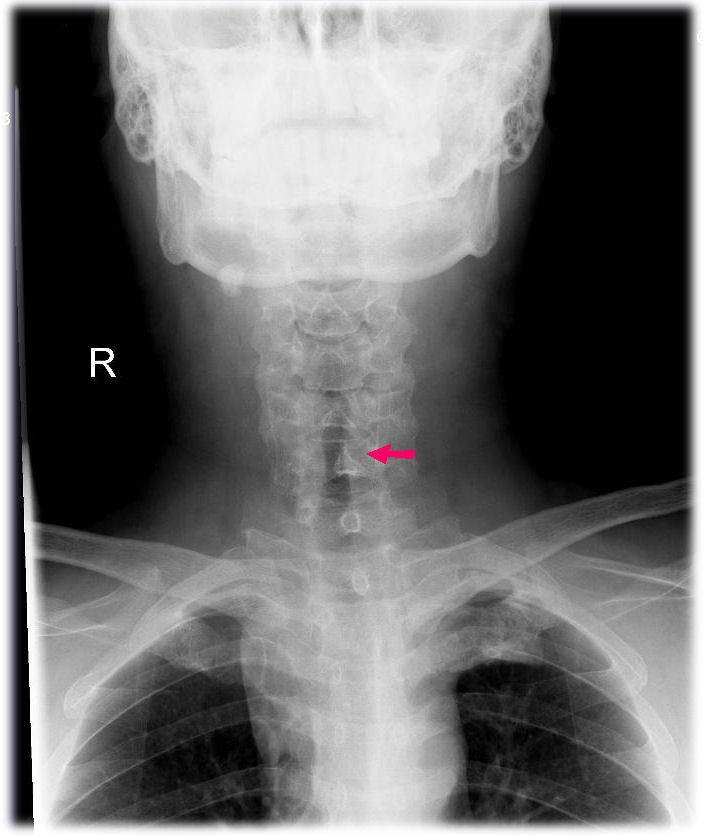

نقش غده تیروئید در بدن چیست؟غده تیروئید در دو طرف نای و کمی در جلوی گردن قرار دارد. این غده هورمون تیروئید ترشح می کند که عملکرد های بدن مانند ضربان قلب، سطح انرژی و وزن را کنترل می کند. هورمون دیگری که توسط غده تیروئید تولید می شود کلسی تونین است که به بدن در کنترل تعادل کلسیم کمک می کند.

در عمل جراحی پاراتیروئید که پاراتیروئیدکتومی نام دارد، یک یا چند غده تیروئید برداشته میشوند. غدد پاراتیروئید، چهار غده به اندازه یک دانه برنج هستند که در پشت غده تیروئید در گردن، قرار دارند. این غدد وظیفه تولید هورمون پاراتیروئید (PTH) را بر عهده دارند که مقدار کلسیم در بدن را تنظِم میکند.